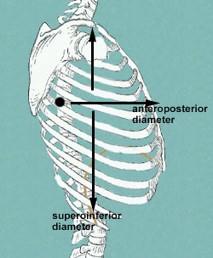

describe what the external intercostal muscles do during inhalation? what do the ribs do? what does the sternum do?

what does the diaphragm do?

the external muscles contract causing the expansion of the chest cavity and an influx of air into the lungs

ribs elevate

sternum flares

diaphragm moves inferiorly during contraction

inspiration while at rest and not exercising involves what 2 muscles?

with exercise what 3 muscles can help out with inspiration?

diaphragm and external intercostals

accessory muscles like the SCM and scalenes can help...pecs can also help

expiration while at rest and not exercising involves what?

with exercise what muscles get recruited to help with expiration?

- rest...elastic recoil of the lungs

- exercise...recruit the internal intercostals + abdominal muscles like (rectus abdominis, int/ext oblique)